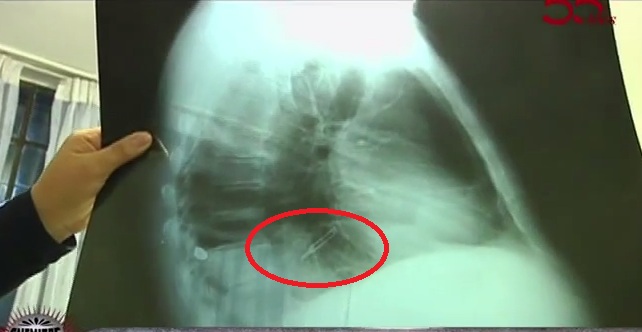

Abraham Arana fue baleado por delincuentes hace cuatro meses y luego tuvo que ser operado dos veces en los hospitales Luis Negreiros y Alberto Sabogal,donde quedó con un bisturí dentro del cuerpo.